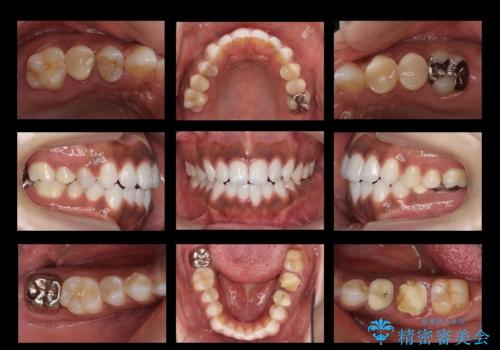

[ 再生治療・歯周外科・小矯正・セラミック補綴 ] 前歯の歯周病治療

担当医 大元洋佑